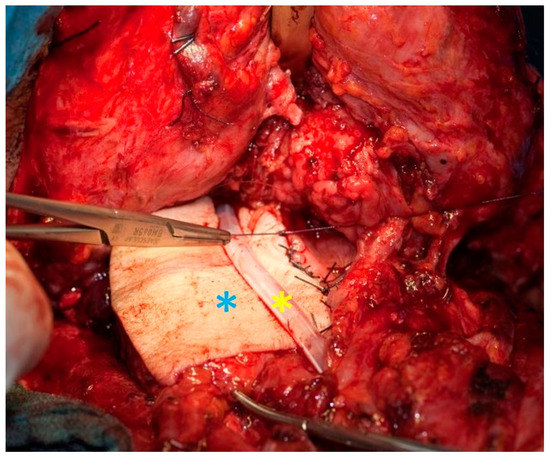

Figure 5.

Patient with a pharyngocutaneous fistula (left, blue asterisk = fistula, yellow = stoma) after salvage laryngectomy and closure of the fistula with a deltopectoral pedicle flap (right, blue asterisk = flap, yellow = stoma).